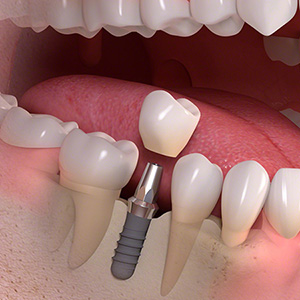

インプラントは、失った歯の部分の骨にチタン製のネジを植え込み、その上に歯の被せ物を乗せる構造をしています。

インプラントの一番の特徴は、入れ歯やブリッジと違い他の歯に迷惑をかけないところです。入れ歯の様に健康な歯にフックをかけたり、ブリッジの様に前後の歯を削らなくて済むので長い目で見ると一番周りの歯に優しく、長持ちすることが論文でも証明されています。 また、本来の歯の形と同じ形状大きさをしているので、異物感もなく自分の歯の様に噛むことが可能です。 |

インプラントと骨が結合するまで時間がかかるので治療期間が長くなります。 骨の中にチタン製のネジを入れるため外科処置が必要です。 |